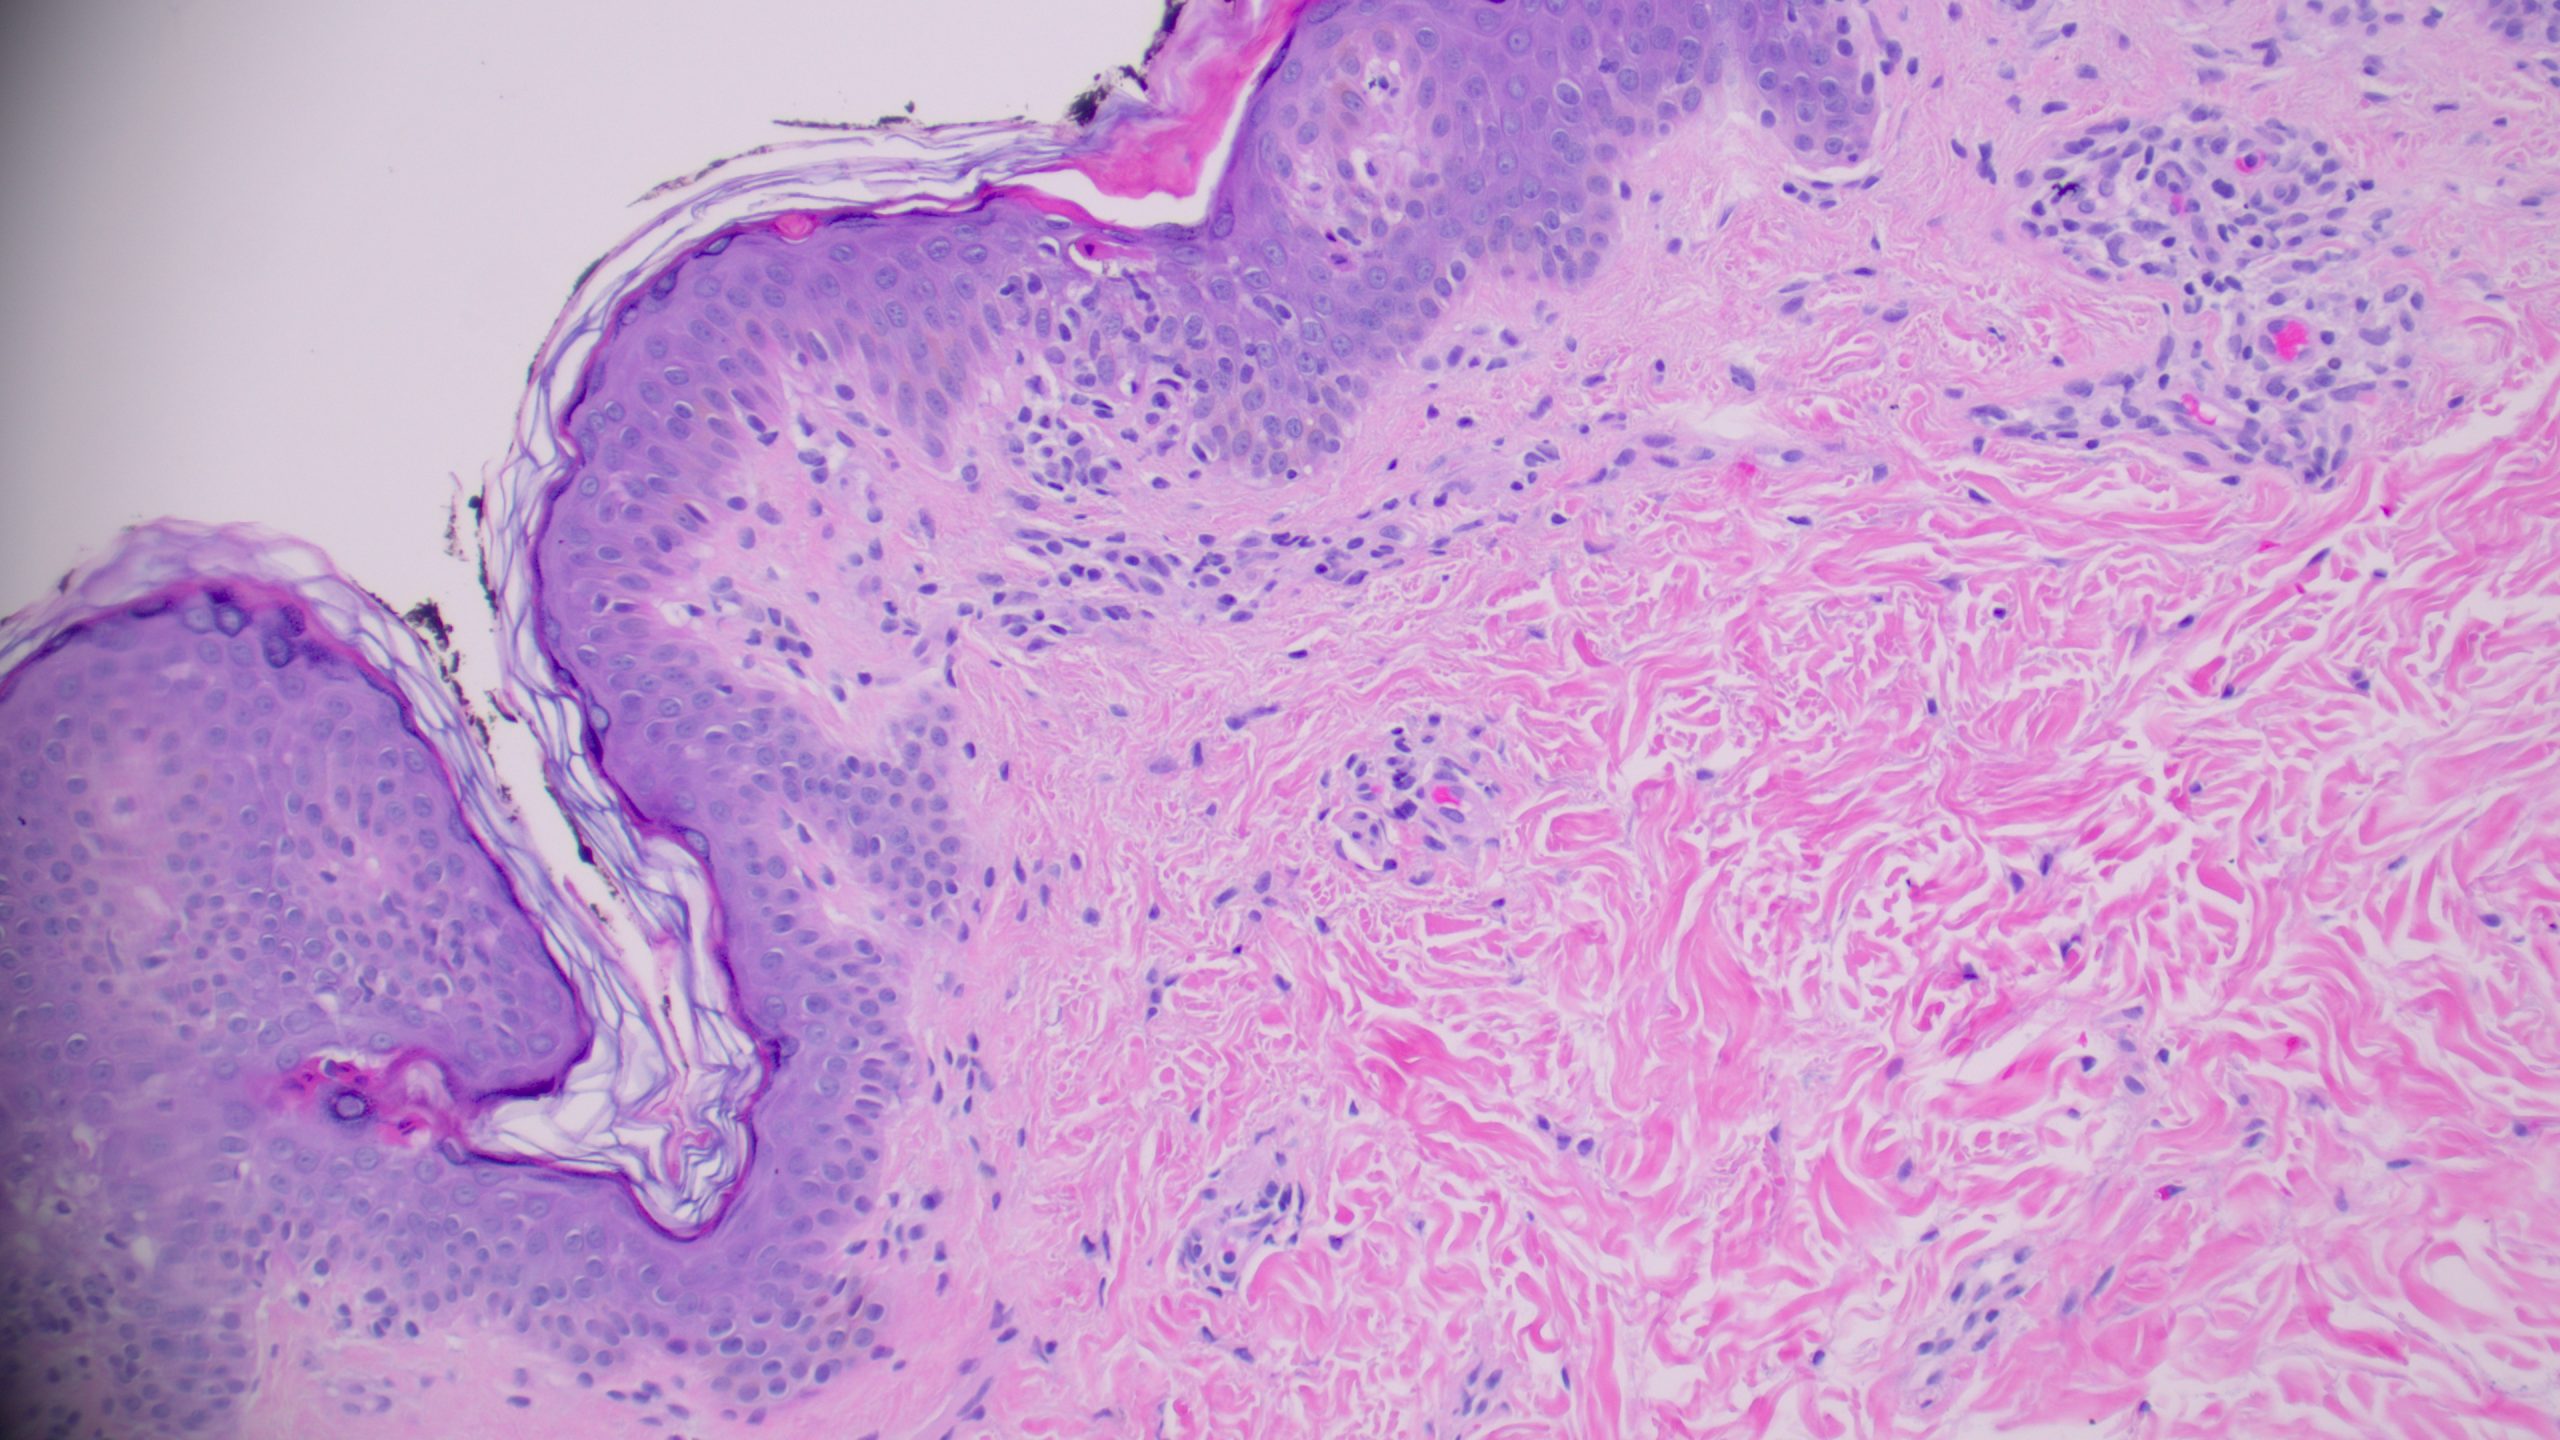

(Medium power showing wedge-shaped perivascular lymphocytic infiltrate)

When evaluating a papular rash with a wedge-shaped infiltrate like this, several differentials come to mind. Let’s walk through the three most likely contenders and highlight what sets them apart.

Pityriasis Lichenoides et Varioliformis Acute (PLEVA)

The combination of a wedge-shaped perivascular lymphocytic infiltrate, necrotic keratinocytes in the epidermis with overlying parakeratosis, and erythrocyte extravasation into the epidermis and superficial dermis is diagnostic of PLEVA. This triad, together with the clinical picture of a young patient with a diffuse papular rash on the trunk, clinches the diagnosis. PLEVA commonly affects patients under 30 years of age, with lesions involving the trunk and proximal extremities presenting as red-brown, mildly pruritic papules that may form blisters, crusts, or ulcers.